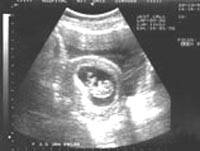

Во Вьетнаме удачно прошла операция по удалению паразитического близнеца из живота семилетней девочки, которая поступила в больницу 16 октября с жалобами на боли в животе. При обследовании в брюшной полости девочки была обнаружена крупная опухоль.Завершившаяся без каких-либо осложнений двухчасовая операция прошла в субботу в детской больнице южной провинции Вьетнама Донгнай. В ходе операции по удалению новообразования выяснилось, что оно представляет собой паразитического близнеца: у недоразвитого плода имелся сформированный позвоночник, руки и ноги, внутренние органы, но отсутствовал головной мозг. Длина тела близнеца, занимавшего почти половину брюшной полости девочки, составляла 20 сантиметров, а вес достигал 1,2 килограммов. Так называемые паразитические близнецы могут образовываться на ранних этапах внутриутробного развития в результате слияния эмбрионов, когда тело одного из них полностью поглощается телом другого. В начале октября хирурги Вьетнамского национального госпиталя в Ханое провели аналогичную операцию, удалив близнеца-паразита шестимесячной девочке. |